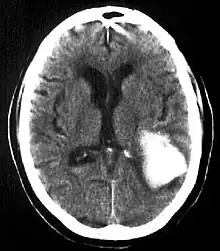

| Multiple intraparenchymal hemorrhage | |

Intraparenchymal hemorrhage is one form of intracerebral bleeding in which there is bleeding within brain parenchyma. The other form is intraventricular hemorrhage).[1]

Intraparenchymal hemorrhage accounts for approximately 8-13% of all strokes and results from a wide spectrum of disorders. It is more likely to result in death or major disability than ischemic stroke or subarachnoid hemorrhage, and therefore constitutes an immediate medical emergency. Intracerebral hemorrhages and accompanying edema may disrupt or compress adjacent brain tissue, leading to neurological dysfunction. Substantial displacement of brain parenchyma may cause elevation of intracranial pressure (ICP) and potentially fatal herniation syndromes.